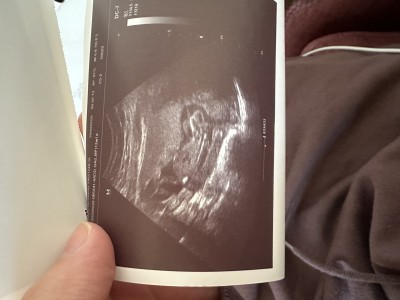

Ultroson resmini yukledim 13 haftaliken doktor daha cok erkege benziyor diye soyledi sizin gorusleriniz nedir? 3 hafta sonra tekrar randevum var 💛

Gebelik haftası 13+5